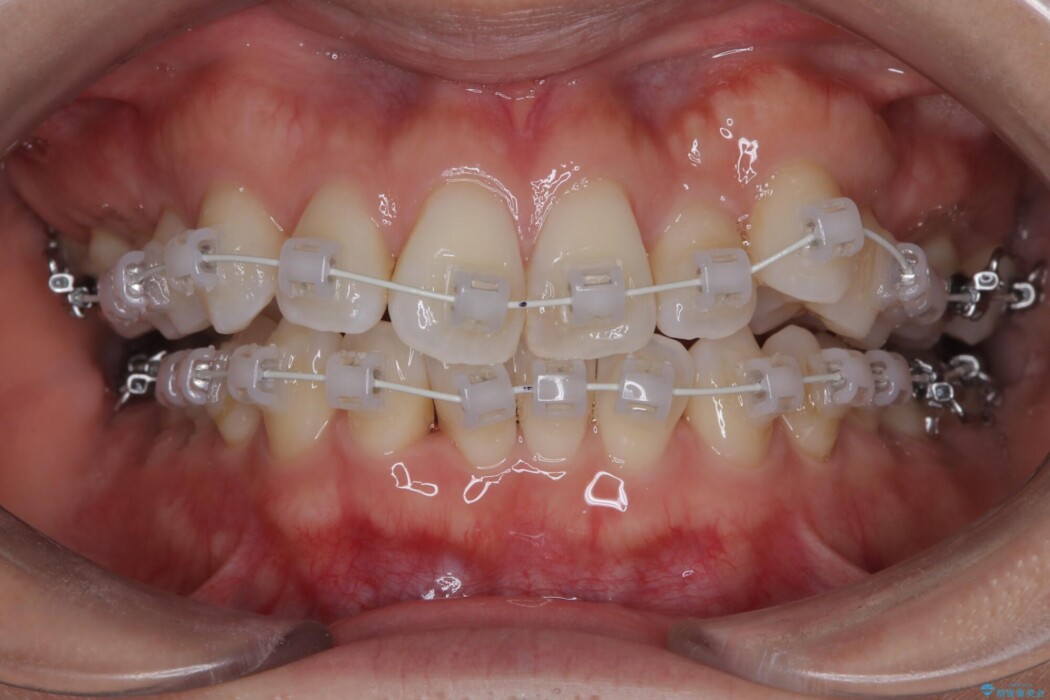

- 矯正装置:ワイヤー(審美装置)

矯正装置は目立ちにくい審美ワイヤーを使用しています。